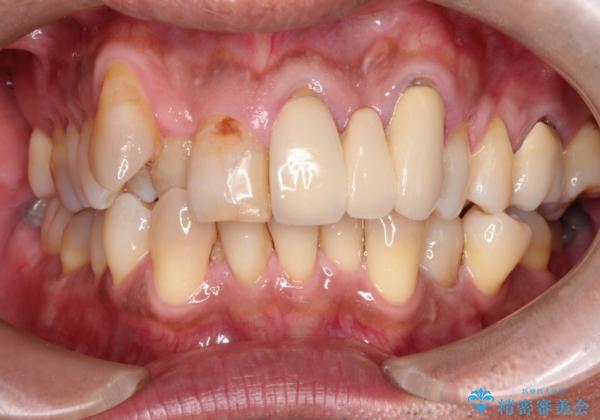

- 50代の患者様で、右上の八重歯と歯並びの乱れを気にされてご来院されました。特に、すでに装着されている前歯のセラミックブリッジを外したくないという強いご希望がありました。精密な検査の結果、八重歯を治すためのスペースが不足しているため、右上の4番目の歯(小臼歯)を抜歯し、そのスペースを利用して歯並び全体を整える治療計画を立案。装置には目立たないインビザラインを採用し、ブリッジを温存しながら八重歯の改善を目指しました。

今回の治療で最も重要だったのは、患者様のご要望通り既存のセラミックブリッジを外さずに矯正を進める点でした。計画通り右上の小臼歯を抜歯し、透明なインビザラインを使用して抜歯スペースを閉じながら、八重歯を正しい位置へ移動させました。ブリッジの形態と調和するに、他の歯の移動を工夫をすることで、複雑な条件をクリア。治療の結果、長年気にされていた八重歯が解消され、見た目が大きく改善しました。50代からでも、ご自身の要望を叶えながら、美しく機能的な歯並びを獲得していただけました。